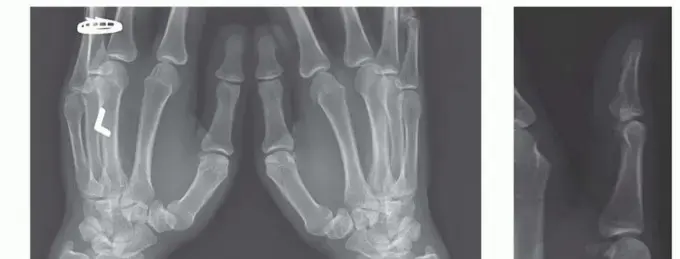

كيف تتم العملية

تُجرى العملية عادة تحت التخدير الموضعي أو العام، وتتضمن الخطوات التالية:

1. شق جراحي صغير: يتم عمل شق صغير ودقيق في قاعدة الإبهام.

2. قطع العظم: باستخدام أدوات جراحية متخصصة، يقوم الجراح بقطع دقيق في عظم المشط الأول (الإبهام) بالقرب من قاعدته.

3. إعادة التموضع والتثبيت: يتم إعادة تموضع الجزء المقطوع من العظم بزاوية معينة لتحقيق الاستقرار المطلوب. ثم يتم تثبيت العظم في موضعه الجديد باستخدام ألواح ومسامير صغيرة مخصصة. هذه الألواح والمسامير عادة ما تكون دائمة ولكن يمكن إزالتها في وقت لاحق إذا لزم الأمر.

4. إغلاق الجرح: يتم إغلاق الشق الجراحي بعناية.

الأستاذ الدكتور محمد هطيف يستخدم أحدث التقنيات وأكثرها دقة لضمان أفضل النتائج بأقل قدر من التدخل، مما يسرع عملية التعافي.